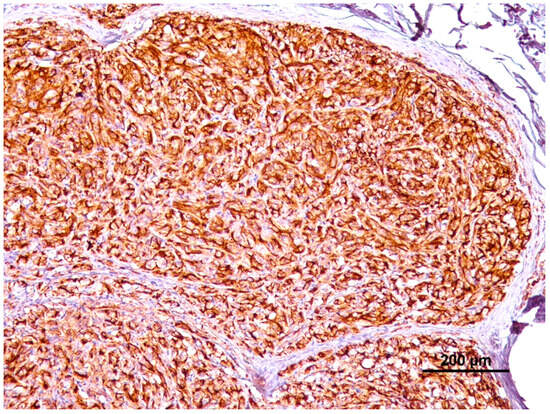

3.3. Immunohistochemical Results

| Immunohistochemistry | Benign (n = 39) | Malignant (n = 38) | Total (n = 77) | |

|---|---|---|---|---|

| Extension | 0 (negative cells) | 3 | 0 | 3 |

| 1 (<10% cells) | 2 | 1 | 3 | |

| 2 (10–25% cells) | 3 | 0 | 3 | |

| 3 (25–50% cells) | 9 | 13 | 22 | |

| 4 (>50% cells) | 22 | 24 | 46 | |